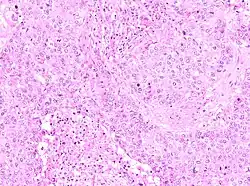

The microscopic histopathology of PACB tumors prepared with hematoxylin and eosin staining shows that >90% of the tumors consist of apocrine gland-like tissue. The lesions must also show that tumor cells have broken through their ducts of origin to invade adjacent tissue in at least one area. Most of the tumor cells (termed type A cells[15]) typically appear somewhat more irregular than normal apocrine gland cells. They have abundant eosinophilic (i.e. pink due to the uptake of the eosin dye) cytoplasm which contain numerous granules[11] and large mitochondria.[15] Their nuclei are large, variably sized and shaped, have multiple nucleoli (which are eosinophilic[11] and may be distinctively large in size[14]), and are surrounded by highly visible nuclear membranes. The cells are arranged into solid sheets, nests, papillae, and/or cords (see Figs. 1 and 2).[11] The tumor cells' cytoplasmic granules test positive when treated with the PAS diastase stain.[16] Binucleated cells, i.e. cells with two nuclei, are common.[10] Less commonly, type B apocrine cells are present; these cells have a more foamy and vacuolated cytoplasm (i.e. containing multiple vacuoles) than type A cells[15] and often resemble foamy histiocytes or sebaceous gland cells.[17] The tumor cells have low to moderate rates of proliferation based on their Ki-67 protein levels.[7] PACB tissues may have localized areas that contain mucin-like secretions within their luminal ducts,[10] localized areas of necrosis (i.e. foci containing dead or dying cells), and/or microcalcifications spotted throughout the apocrine tissue.[11] The stroma (i.e. connective tissue between the sheets, nests, papilla and cords of cells) typically contains non-malignant, infiltrating lymphocytes (see Fig. 3). In an examination of 41 PABC tumors, 33 (80.5%) had <50% of their stroma tissues infiltrated with these cells while 8 (19.5%) had ≥50% of their stroma tissues infiltrated with them. Tumors with ≥50% of their stroma infiltrated with lymphocytes tended to have carcinoma cells that had high rates of proliferation.[11] Metastatic and recurrent PACB tumors have a histopathology similar to their original primary tumors.[14]